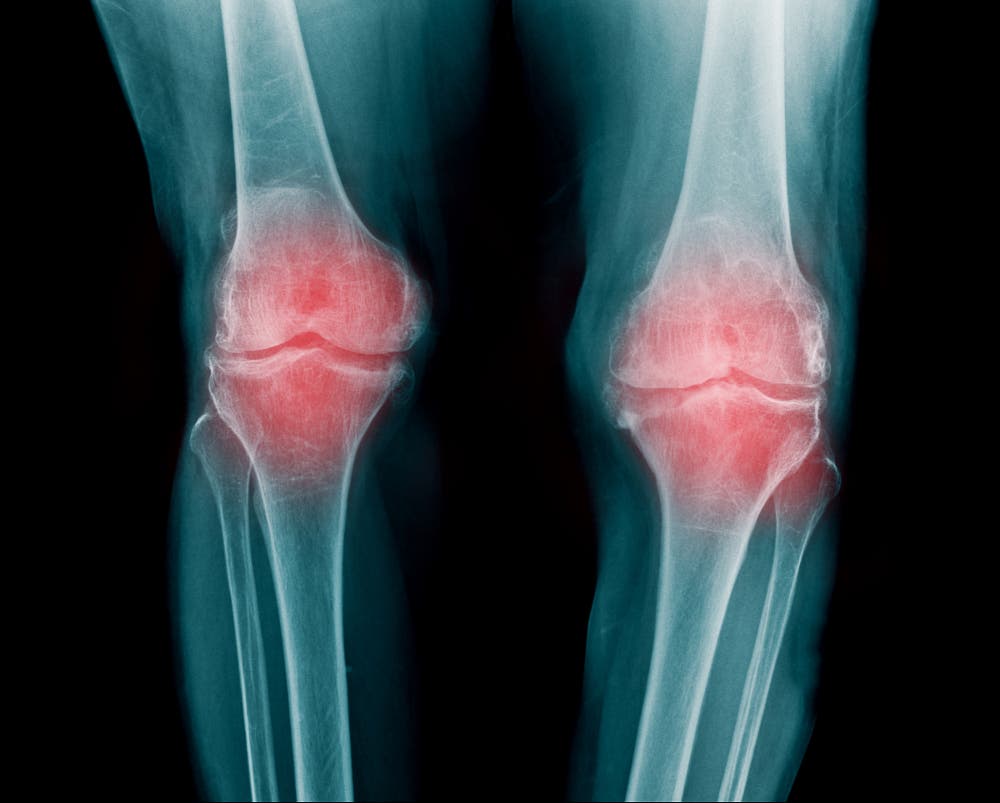

Se la considera una enfermedad asociada a la vejez y con muy poco glamour, si es que alguna enfermedad lo tiene. Sin embargo, la artrosis es una patología muy compleja de y que afecta tanto a personas mayores como a otros grupos de riesgo. Especialmente a las mujeres en edad post-menopáusica, a los deportistas y también a los jóvenes.

Afecta a más de 242 millones de personas en todo el mundo y es una cifra que sigue creciendo debido al aumento de la esperanza de vida, pero también a los malos hábitos en la alimentación, la obesidad, el sedentarismo y el deporte practicado sin control.

La artrosis no sólo causa dolor, sino que está asociada a otras patologías como la diabetes, las enfermedades cardiovasculares, o la hipertensión entre otras.

Una mala evolución de la artrosis puede llevar a falta de movilidad y discapacidad incapacitando a los pacientes para realizar las tareas más cotidianas. Además, las personas con artrosis, sobre todo las mujeres tienen más riesgo de sufrir otras patologías como ansiedad o depresión que las que no la padecen [Estudio EMATRO].

En este contexto, la Sociedad Internacional de Investigación en Artrosis (OARSI en sus siglas en inglés) ha solicitado a la Agencia Americana del Medicamento (FDA) que considere la artrosis como una enfermedad grave a través del libro blanco: Artrosis, una enfermedad grave [OARSI white paper. Osteoarthritis: A serious disease].